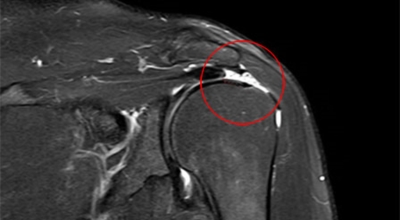

2. 수술적 치료

힘줄의 전층 파열이 발생하던가 외상성 파열, 활동성이 많은 젊은 경우에는 지날수록 기능 이상이 발생하던가 근력 저하를 동반할 우려가 있는 경우 수술적 치료를 시행하게 되어요. 수술 치료는 파열된 힘줄을 봉합하며 관절경을 이용한 봉합술이 대표적입니다. 파열 정도와 부위에 따라 봉합이 불가능하던가 재파열될 확률도 있고 이로 인해 움직임에 제한이 발생되는 노인인 경우에는 인공 관절 수술을 시행할 수도 있다고 하죠.